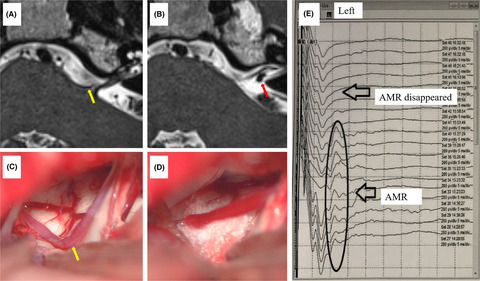

DEX-induced inhibition of P2X3 receptor-mediated ATP currents in DRG neurons. (A) Two original currents were evoked by 100 μM α,β-meATP and 100 μM ATP, separately, in the same DRG cell. These currents were blocked by 300 μM A-317491 (a specific P2X3 and P2X2/3 receptor antagonist), but not by 10 μM PSB-12062 (a P2X4 receptor antagonist) and 1 μM A438079 (a potent P2X7 receptor antagonist). Membrane potentials were clamped at −60 mV. (B) Pre-application of DEX (3 μM for 5 min) to a DRG cell inhibited 100 μM α,β-meATP- and 100 μM ATP-induced currents similarly. (C) The sequential current traces illustrated that the amplitude of the 100 μM α,β-meATP-induced currents progressively decreased after a representative DRG cell was pre-treated with increasing concentrations of DEX. DEX was pre-applied to DRG tested for 5min. (D) The graph showed the concentration-effect curve of DEX on inhibition of 100 μM α,β-meATP-induced currents (IATP). The IC50 value of the curve was 1.12 ± 0.16 μM. Each point represents the mean ±SEM of 8–10 cells

In some DRG neurons, we pre-treated with DEX for 5min prior to the next IATP recording. As shown in Figure 1B, DEX pretreatment (3 μM) decreased the peak amplitudes of both α,β-meATP- and ATP-activated currents. Figure 1C shows that the peak amplitudes of 100 μM α,β-meATP-activated currents decreased as the concentration of DEX increased from 0.1 μM to 10 μM in a representative DRG cell. Figure 1D shows concentration-effect curve of DEX on IATP with an IC50 (half-maximal effective concentration) value of 1.12 ± 0.16 μM. The results suggested that DEX inhibited P2X3 receptor-mediated ATP currents in a concentration-dependent manner.